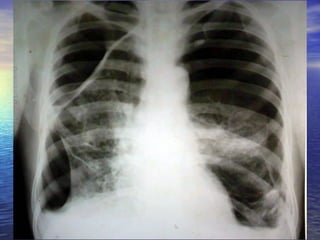

CHEST X RAY PA VIEW ADEQUATE INSPIRATION CENTRING, PATIENT POSITION -  NORMAL EXPOSURE/PENETRATION -  ADEQUQTE TRACHEA POSITION -  MIDLINE HEART AND MEDIASTINUM –  NORMAL PLEURAL SPACE  –  HYDROPNEUMOTHORAX  ON THE LEFT SIDE  EVIDENCED BY THE CONVEX  OUTSIDE BORDER OF  LUNG WITH VISCERAL PLEURA AND AIR FLUID LEVEL ? BULLAE/ ?LOCULATED HYDROPNEUMOTHORAX  SEEN  ON RIGHT SIDE EVIDENCED BY CONVEX INWARDS  MARGINS OF THEIR WALLS WITH AIR FLUID LEVEL COSTOPHRENIC ANGLES  BLUNTED BILATERALLY  CARDIOPHRENIC ANGLES  FREE HILA DENSITY, POSITION, SHAPE -  NORMAL SOFT TISSUES –  NORMAL BONES-  NORMAL Imp:LEFT HYDROPNEUMOTHORAX  RIGHT BULLOUS DISEASE/HYDROPNEUMOTHORAX WITH ?PLEURAL THICKENING

CHEST X RAYPA VIEW ADEQUATE INSPIRATION CENTRING, PATIENT POSITION - NORMAL EXPOSURE/PENETRATION - ADEQUQTE TRACHEA POSITION - MIDLINE HEART AND MEDIASTINUM – NORMAL PLEURAL SPACE – HYDROPNEUMOTHORAX ON THE LEFT SIDE EVIDENCED BY THE CONVEX OUTSIDE BORDER OF LUNG WITH VISCERAL PLEURA AND AIR FLUID LEVEL ? BULLAE/ ?LOCULATED HYDROPNEUMOTHORAX SEEN ON RIGHT SIDE EVIDENCED BY CONVEX INWARDS MARGINS OF THEIR WALLS WITH AIR FLUID LEVEL COSTOPHRENIC ANGLES BLUNTED BILATERALLY CARDIOPHRENIC ANGLES FREE HILA DENSITY, POSITION, SHAPE - NORMAL SOFT TISSUES – NORMAL BONES- NORMAL Imp:LEFT HYDROPNEUMOTHORAX RIGHT BULLOUS DISEASE/HYDROPNEUMOTHORAX WITH ?PLEURAL THICKENING